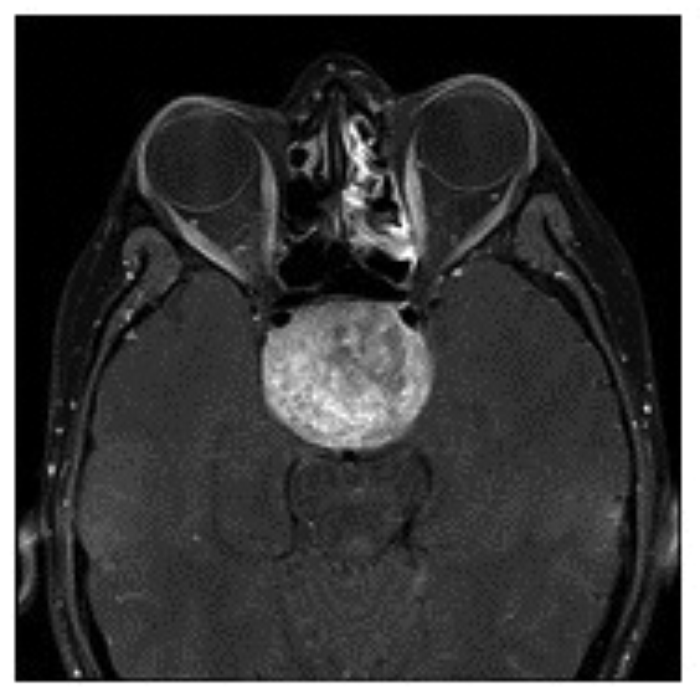

A 26-year-old primary school teacher with 10 diopters of myopia was referred to the laser centre for evaluation prior to possible treatment. He had been seen since his school days by a number of different optometrists because of his high myopia and appropriate spectacles were prescribed and later contact lenses. In the laser centre he was noted to have a significant degree of exo deviation (exophoria / exotropia) so the opinion of a motility specialist was arranged, who advised surgical treatment. On further questioning he admitted to having intermittent headache and even though the optic discs were considered to be normal for his degree of myopia fortunately a brain scan was advised prior to the proposed surgery. The result of MRI scan is shown in Figure 5.

Figure 5: MRI scans of the 26-year-old myopic patient showing a large pituitary tumour.

Top = Axial image. Middle = coronal image. Bottom = saggital image.

In the neuro-ophthalmology clinic he again denied any subjective visual problems apart from those associated with his high myopia. His acuity was confirmed as 6/6 N5 in each eye with normal colour vision, and the optic discs again could have been considered within normal limits for his degree of myopia. Now at last at this, his 16th eye examination, a confrontation visual field was performed and a complete bitemporal hemianopia easily elicited. Formal visual fields confirmed the bitemporal hemianopia with contraction of the residual nasal fields (Figure 6). His prolactin level was normal so he was referred urgently to neurosurgery. His trans-sphenoidal hypopysectomy extended to over three hours as a solid type tumour was encountered which was not possible to remove completely. At follow-up there was no improvement in his visual field defect but, as expected post-operation, the optic discs were now pathologically pale. He is on replacement hormonal treatment and requires long-term follow-up in endocrine, neurosurgical and neuro-ophthalmology clinics.